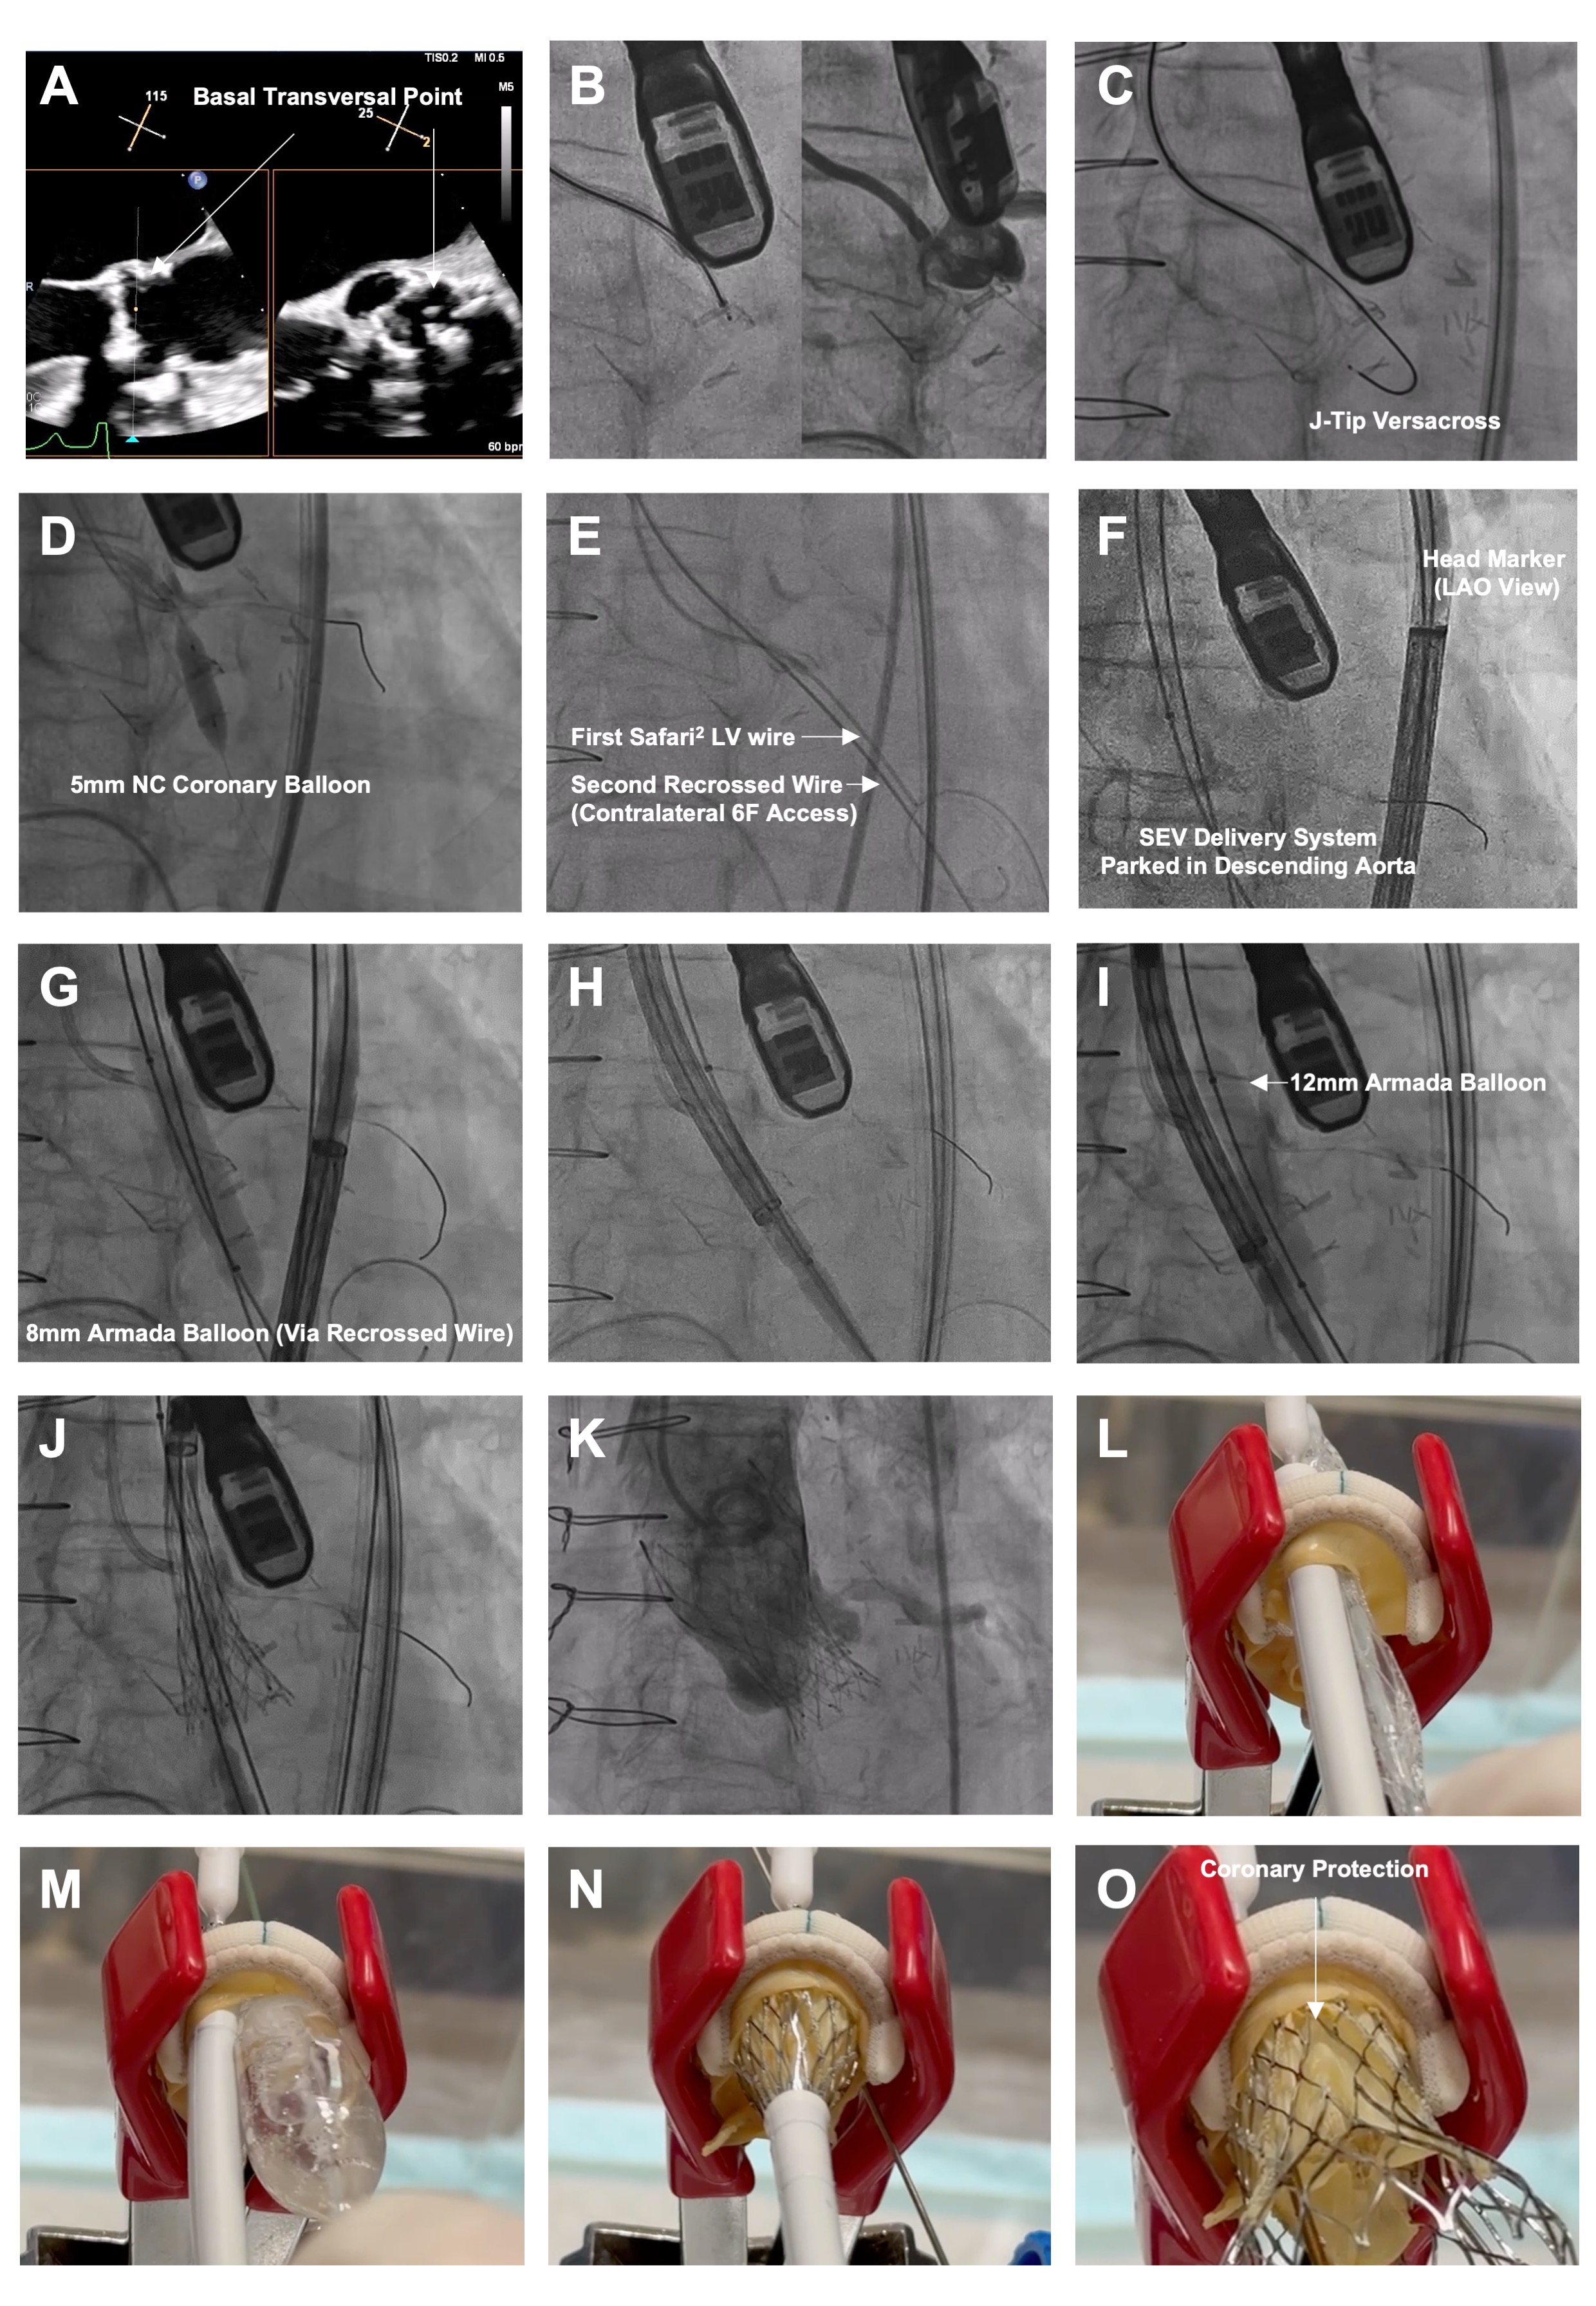

- Position a 7F guide (left: Amplatz Left 1/2; right: Multipurpose), 135-cm NaviCross catheter (Terumo), and 0.035-inch J-tip VersaCross wire (Boston Scientific) at the base of the target leaflet (Figure A and B). Traverse with radiofrequency (Figure C), cross the microcatheter, and exchange for a 300-cm coronary guidewire.

- Dilate fenestration with a 5-mm noncompliant coronary balloon (Figure D). Cross the microcatheter and exchange for a pre-shaped stiff wire. Recross the fenestration from contralateral 6F access with a second guidewire (0.035-inch straight-tip EMERALD [Cordis] or J-tip [Terumo]), using a similar 7F guide (Figure E). Exchange the second wire for an Amplatz Extra Stiff (Cook Medical).

- Deliver an Evolut FX+ valve (Medtronic) via primary access to the descending aorta, with the head marker oriented along the outer curvature under left anterior oblique projection to facilitate commissural alignment (Figure F).

- Dilate the fenestration with an 8-mm peripheral balloon via contralateral access (Figure G); this facilitates subsequent crossing of the SEV. The target leaflet is not lacerated at this stage.

- Position a 12-mm peripheral balloon and the SEV delivery capsule side by side across the fenestration. (Figure H). Gradually inflate the balloon until “give-way,” indicating leaflet laceration (Figure I). Deploy the SEV (Figure J) and simultaneously deflated balloon, and withdraw the guidewire. Controlled pacing may enhance stability. Near-simultaneous leaflet laceration and SEV deployment preserves hemodynamics; it also entraps the lacerated leaflet and places it away from the coronary ostium if the balloon pushes the SEV toward the annulus. (Figure-1K/1L)

- If the leaflet is lacerated during the second balloon dilatation, withdraw the balloon and advance the SEV from the aorta for seamless deployment.

In conclusion, the UNICORN with recrossing technique enables seamless leaflet laceration and SEV deployment (Figure M-O).